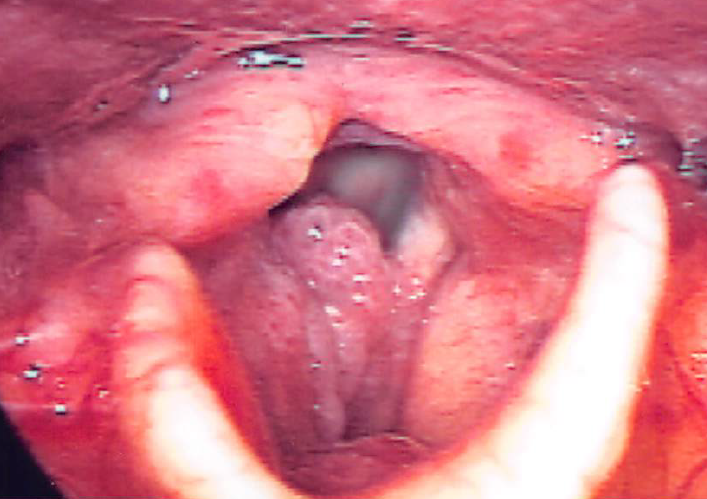

扁桃肥大とは

喉の奥にある扁桃(口蓋扁桃)が何らかの原因で肥大してしまう病気で、呼吸がしにくく、いびきや無呼吸症候群の原因にもなります。また、食事を飲み込むのに時間がかかります。治療には手術が必要な場合もあります。

喉の奥にある扁桃(口蓋扁桃)が何らかの原因で肥大してしまう病気で、呼吸がしにくく、いびきや無呼吸症候群の原因にもなります。また、食事を飲み込むのに時間がかかります。治療には手術が必要な場合もあります。